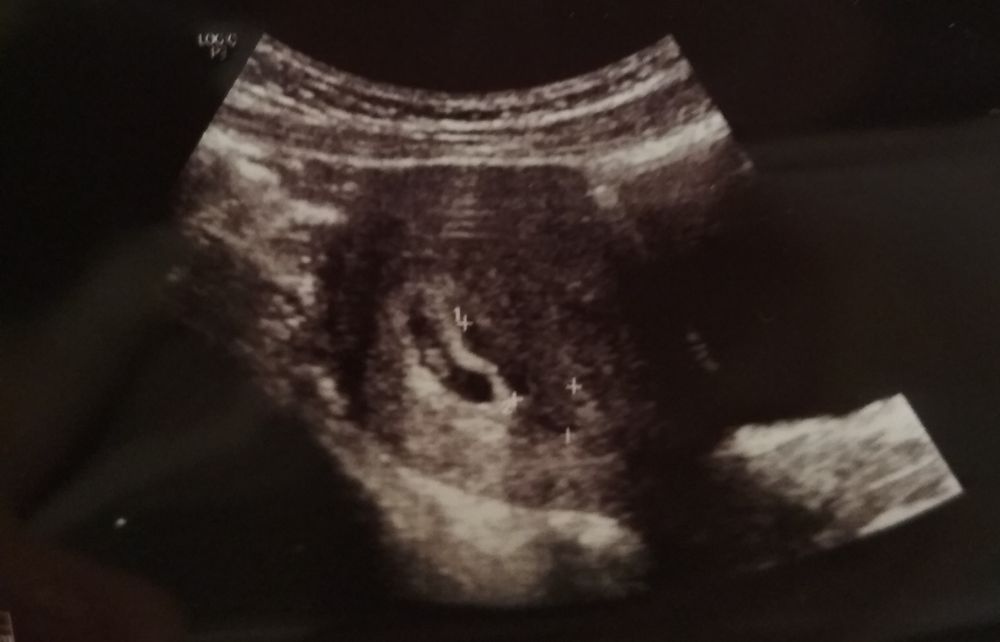

Гематома 25 мм в 6н 5д.

На сохранении лежала, немаленькая